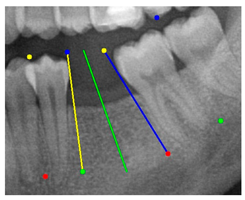

The angle bisector of the two auxiliary lines was then calculated using the angle bisector formula shown in (8), where (, , ) and (, , ) represent the coefficients of the two lines. The resulting internal angle bisector defines the preliminary implant pathway orientation derived by this framework. This bisector represents the most stable implant pathway orientation direction, ensuring that the implant avoids adjacent teeth and critical anatomical structures while maximizing bone–implant contact area. Such orientation enhances osseointegration stability and prevents complications from improper angulation, such as malocclusion or uneven stress distribution. The visualization of this process and the algorithmic design are presented in Figure 8. Finally, the auxiliary pathway generated by the algorithm was compared and overlapped with the implant pathway orientation annotated by dentists on the images to evaluate the predictive capability and accuracy of the model. The overlap results serve as a basis for further model optimization and provide valuable reference information for clinical application.

Figure 8.

Auxiliary lines are derived from adjacent teeth, the blue and yellow line is the result of implant pathway orientation visualization algorithm, and the green is the best implant pathway orientation.

3.3. Comparison with Clinical Ground Truth and AI-Assisted Framework

This subsection presents a comparison between the dentist-defined clinical gold standard and the predictions generated by our AI-assisted framework to evaluate the reliability of implant pathway orientation. The result is shown in Table 10, the preserved DPR validation set was used for verification, and the AI-assisted framework results were overlaid onto the original DPR images to provide a clear visualization. The AI-assisted framework pathways (green lines) were highly consistent with the dentists’ ground-truth annotations (black lines). Quantitatively, the mean squared error (MSE) between the predicted implant direction and the dentists’ planned results was only 1.537° across multiple test images. This minimal deviation validates the proposed system’s technical feasibility. It highlights its clinical potential to provide accurate and stable guidance for implant placement, thereby reducing the risk of misalignment and supporting efficient preoperative orientation.